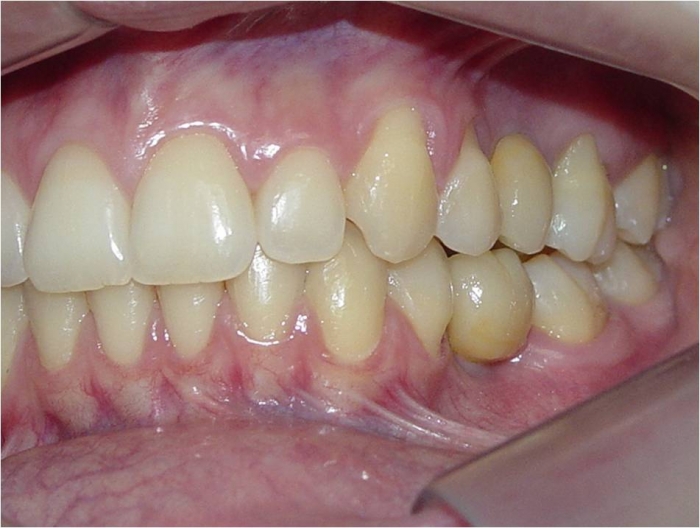

Imagem inicial